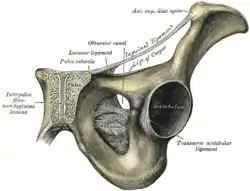

The sacrum and pelvic bone, with parts labelled. The pubic bone consists of the body and superior pubic ramus (4), and the inferior pubic ramus (3), which join at the pubic symphysis. The gap between them is the obturator foramen.

The sacrum and pelvic bone, with parts labelled. The pubic bone consists of the body and superior pubic ramus (4), and the inferior pubic ramus (3), which join at the pubic symphysis. The gap between them is the obturator foramen. Right hip bone. External surface.

Right hip bone. External surface. Right hip bone. Internal surface.